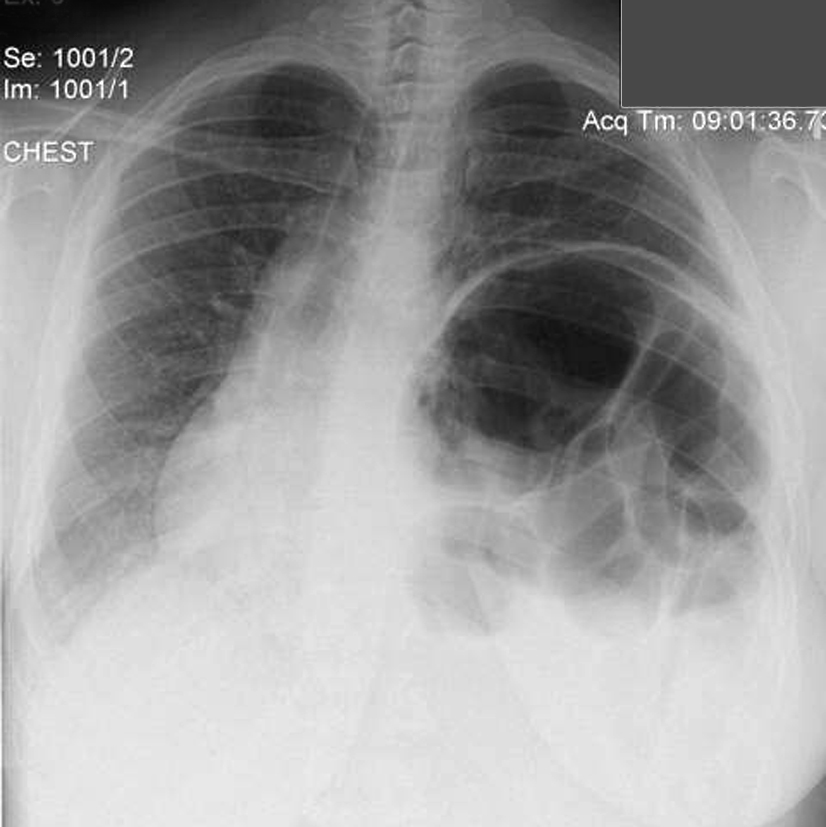

On physical exam she was obese (BMI 34) but in good general condition. There were no abnormalities on the thoracic and abdominal examination other than reduced breath sound at the left lung base. A chest x-ray showed substantial elevation of the left hemidiaphragm (Figure 1). A chest CT showed a massively distended left colon under the left diaphragm (Figure 2). A “sniff test” (fluoroscopic assessment of diaphragmatic function) showed paradoxical motion of the elevated hemidiaphragm.